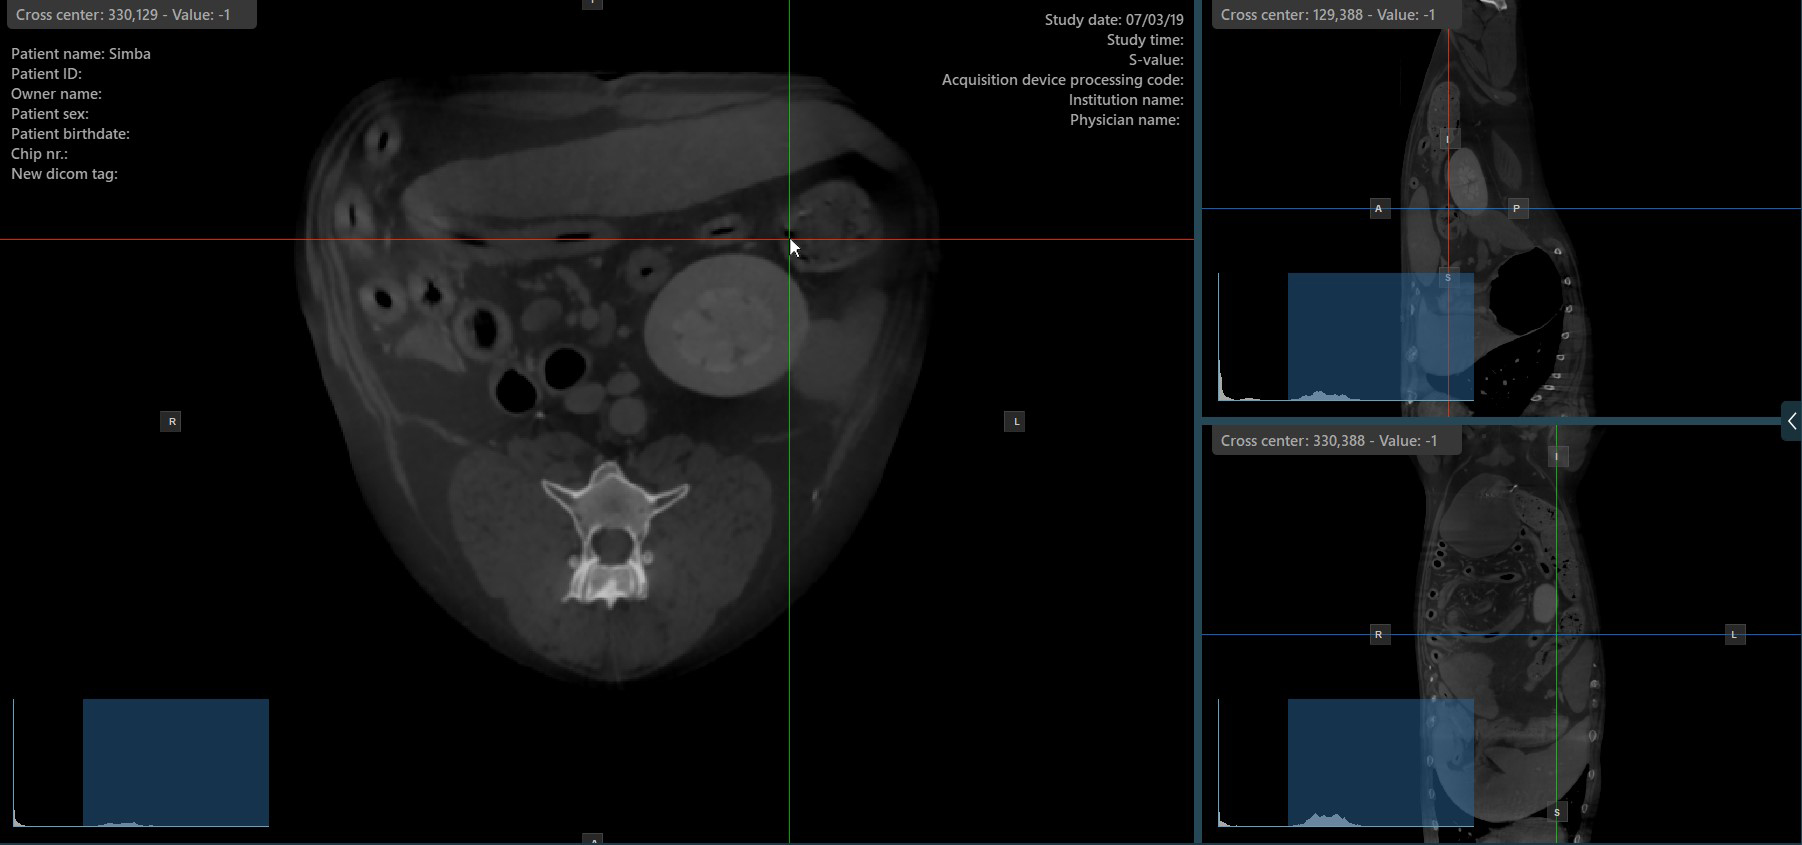

The slicers in MPR view show the intersections and orientation of the three image planes displayed in the active viewports. Users can modify the slicers and change the cross-sectional position of the slices based on the 3D volumetric data.

Each slicers is distinguished by their specific color, which representes the image plane:

The blue slicer marks the axial plane of the object (perpendicular to the ground)

The red slicer marks the coronal plane (parallel to the ground)

The green slicer marks the sagittal plane (perpendicular to the body)

Change Slicers Cross Center Position¶

Altering the position of the cross center of slicers will change the position of the corresponding two image planes. The cross center of the slicers can be selected by using the Select Item (Default) tool, assigned to the right mouse

button by default.

Once selected, drag the cross center of the specific slicers to the desired direction to move its position. The corresponding image planes’ orientation changes accordingly.